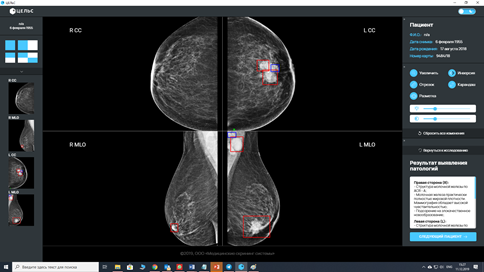

Чтение и интерпретация снимков по BI-RADS

Система помощи принятия решений на основе нейронных сетей и математического анализа

Маммография –

опытная эксплуатация в рамках пилотов.